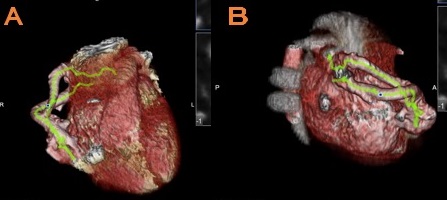

Ante la sospecha de cortocircuito extracardiaco, se realiza angiotomografía computarizada (Fig. 2) que confirma el diagnóstico de malformación arteriovenosa pulmonar (MAVP), con aporte arterial a través de rama de 6 mm de calibre, que se origina de la arteria pulmonar derecha, distal a salida de la arteria lobar superior.

Figura 2. Angiotomografía en la que se observa MAVP